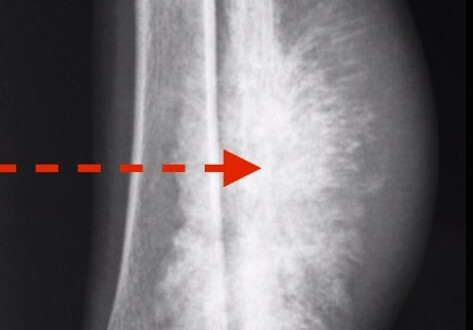

What pathology is shown here?

Osteosarcoma